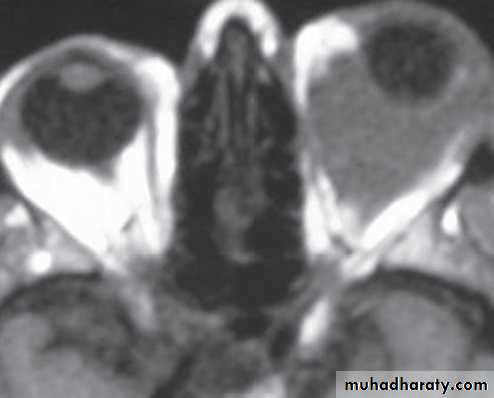

Investigation: CT and MRI show a well circumscribed oval lesion, usually within the muscle cone.

• Investigation: MRI effectively demonstrates the tumour, and may show intracranial extension if present.

• Investigation: MRI is the investigation of choice, CT shows thickening and calcification of the optic nerve.